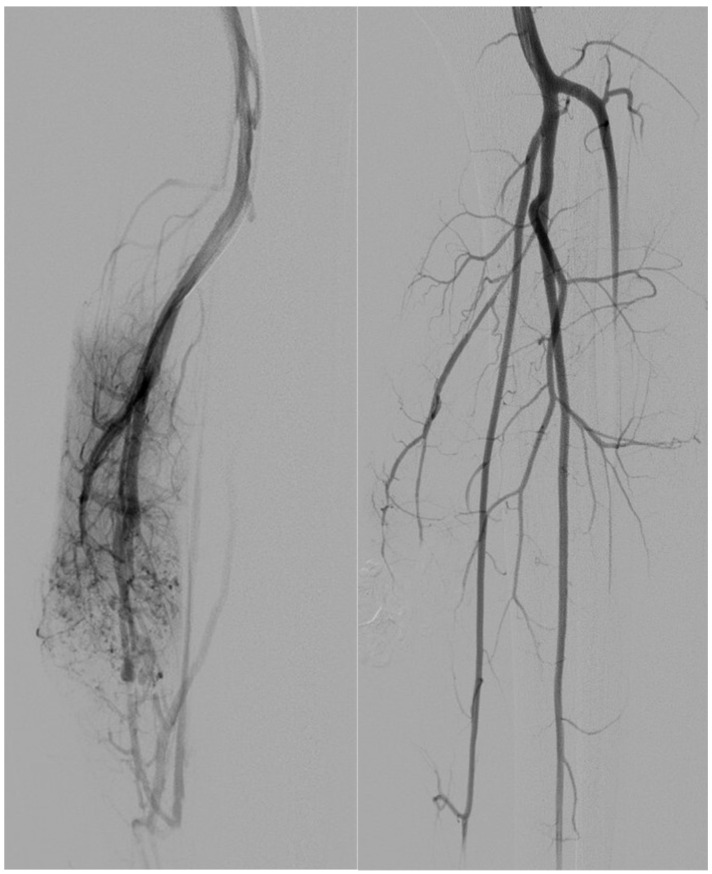

背景:颅外动静脉畸形(AVMs)是一种罕见的先天性血管异常,通常由于疼痛、出血或功能障碍等症状而需要血管内治疗。血管内栓塞包括动脉栓塞、静脉栓塞或联合栓塞;然而,复发仍然是主要的挑战。我们回顾性评价单纯动脉栓塞与动静脉联合栓塞治疗颅外动静脉畸形的技术成功、安全性和临床结果。材料和方法:本单中心回顾性研究纳入14例患者(平均年龄31.8±21.7岁;在2017年至2023年期间,有症状的颅外AVMs (Schobinger II期)治疗的患者占64%(女性)。血管造影对AVMs进行分类(Yakes分类),并通过动脉或联合通路进行栓塞治疗。主要终点是技术成功(定义为血管造影病灶闭塞),次要终点包括临床复发和手术相关并发症。随访包括临床和多普勒超声评估。结果:9例(64%)患者单独行动脉栓塞术;5例(36%)接受动脉和静脉联合栓塞,包括直接穿刺注射聚月桂醇。所有病例均取得了技术上的成功(100%)。2例患者(14%)出现临床复发,均来自单纯动脉组。一个主要的并发症(舌缺血)发生在一个病人身上(7%)。联合治疗组无并发症及复发。统计学分析显示两组患者复发率及并发症发生率无显著差异。

Results: Nine patients (64%) underwent arterial embolization alone; five (36%) received combined arterial and venous embolization, including Lauromacrogol injection via direct puncture. Technical success was achieved in all cases (100%). Clinical recurrence occurred in two patients (14%), both from the arterial-only group. One major complication (tongue ischemia) occurred in a single patient (7%). No complications or recurrences were observed in the combined treatment group. Statistical analysis showed no significant difference in recurrence or complication rates between groups.